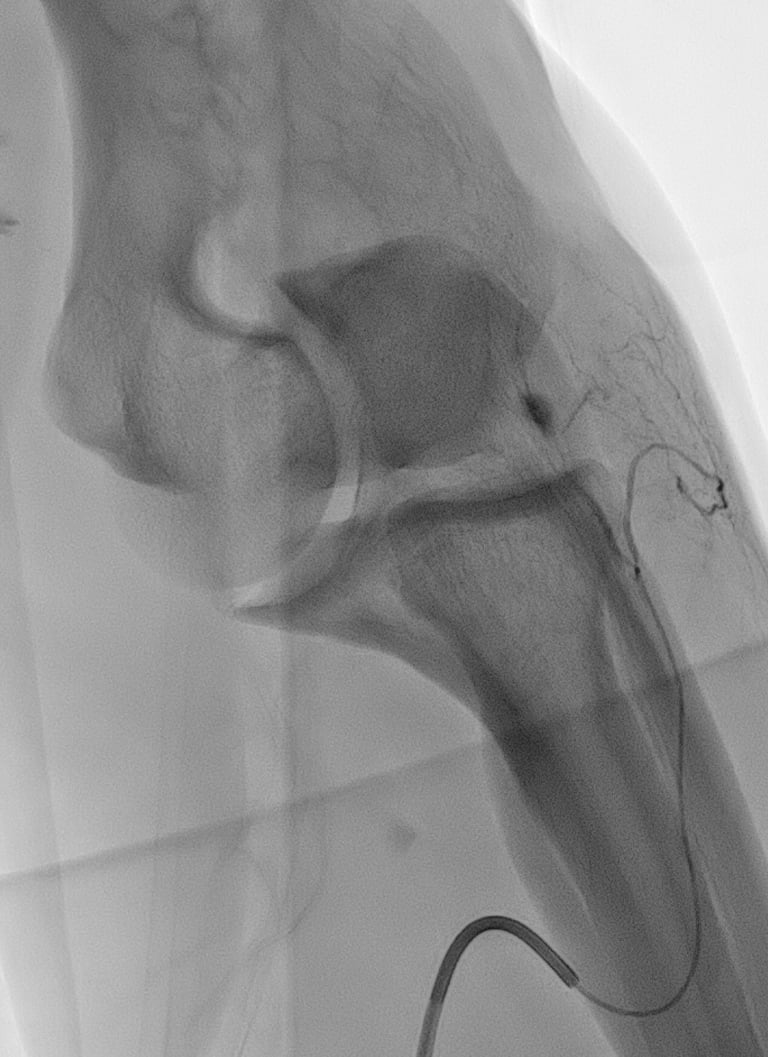

A l’aide d’un abord vasculaire artériel au niveau du poignet ou de la jambe , un cathéter est envoyé dans les vaisseaux de la zone concernée (épaule ou coude le plus souvent).

Une artériographie par injection de produit de contraste iodé est réalisée. Elle permet la cartographie des artères pour dépister les zones d'hypervascularisation, qui sont le témoin de l'inflammation locale. Ces zones sont le plus souvent concordantes avec les douleurs rapportées par le patient.